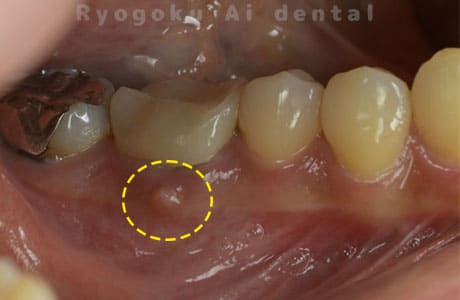

Case03

-

- 原因

- 歯牙破折

- 治療内容

- MTA治療

- 治療費用

- ¥55,000

右下の奥の歯が割れているとのことで他院で抜歯を宣告され、保存希望で当医院来院された患者様です。歯周ポケットもなくなり、現在、問題なく経過しており、患者様も満足されております。

<リスク・副作用>

手術後は痛み、腫れ、痺れ、青あざなどの副作用が生じます。痛みは痛み止めを処方しますが、腫れ、青あざは1週間程度生じる場合があります。また、部位によっては神経の走行が複雑で、痺れが残り、長期的にお薬を処方する場合があります。